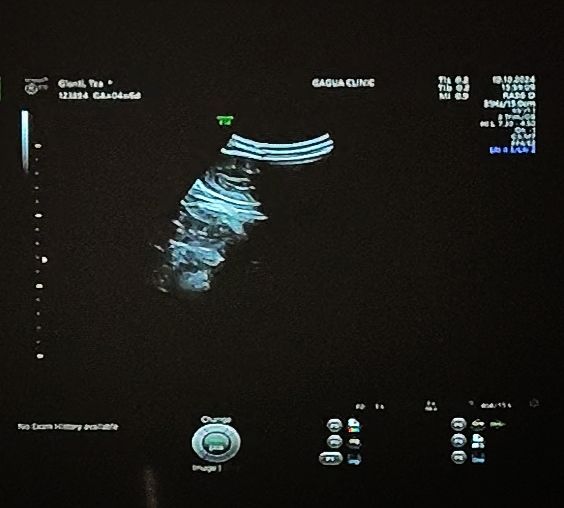

Здравствуйте девочки в общем была на УЗИ сказали что плодное яйцо 2 мм где что как никто ничего не показал никто ничего не объяснил на УЗИ должны повторно сходить пятнадцатого Но уж очень интересно может кто разбирается где тут что???

Кира, на 5 неделе да но это по м. А по зачатию о была позднее на 3-4 дня то есть на тот момент 4 недели 3-4 дня